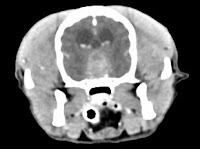

His hyperadrenocorticism has responded well to medical therapy with mitotane. However, over the last few months, the dog developed severe lethargy and inappetence. More recently, he exhibited behavior changes, severe altered mentation, and had a seizure. We did a CT scan (see dog's image above), which confirmed a large pituitary tumor.

No, this is not a good surgical case. Surgery in the right hands (i.e., an experienced neurosurgeon who has done large numbers of hypophysectomies over years with consistent positive results) has been shown to be very effective (3,4). However, this dog's pituitary tumor is just too large and invasive to remove with a transphenoid approach (5). A hypophysectomy would only remove the small portion in the sella, but this dog's problem is the large portion above the sella that's compressing the brain. If you were going to really try to remove this, you would probably need to use a subtemporal skull-base approach. Even if you are an experienced neurosurgeon, I would strongly advise against attempting pituitary surgery in this dog.